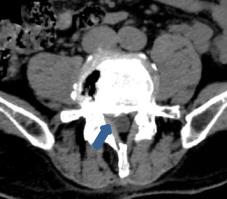

• 脊柱内镜侧后路联合减压术治疗腰神经根双卡综合征的临床疗效观察

2025, 31(12):25-32. DOI: 10.12235/E20250012

摘要 (122) HTML (46) PDF 10.14 M (90) 评论 (0) 收藏

摘要:目的 观察脊柱内镜侧后路联合减压术治疗腰神经根双卡综合征(DCS)的临床疗效、可行性、安全性和有效性。方法 回顾性分析2018年9月-2023年9月于该院就诊的50例腰椎退行性病变致腰神经根DCS患者的临床资料,根据手术方法不同,将患者分为观察组(37例)和对照组(13例)。观察组行脊柱内镜侧后路联合减压术治疗,对照组行非手术治疗。比较两组患者治疗前、治疗后1周、治疗后3个月、治疗后6个月和治疗后12个月的疼痛视觉模拟评分法(VAS)评分、Oswestry功能障碍指数(ODI)和日本骨科协会(JOA)评分。末次随访时,采用改良Macnab标准,评估临床疗效;采用腰椎MRI检查,评估椎间隙高度和椎间盘退变改良Pfirrmann分级。比较两组患者治疗的安全性(包括:并发症发生情况、复发情况和转手术治疗情况)。结果 50例患者均顺利完成治疗。两组患者术后VAS评分和ODI呈下降趋势,JOA评分呈升高趋势,观察组术后各时点VAS评分和ODI明显低于术前,且明显低于对照组,术后各时点JOA评分明显高于术前,且明显高于对照组,差异均有统计学意义(P < 0.05);观察组优良率为86.49%,明显高于对照组的76.92%,差异有统计学意义(P < 0.05);两组患者末次随访时,椎间隙高度和椎间盘退变Pfirrmann分级比较,差异均无统计学意义(P > 0.05)。两组患者围手术期均未出现神经损伤和脑脊液漏等严重并发症,观察组术后1例出现下肢放射性疼痛;观察组1例术后3个月出现腰椎间盘再突出;对照组有3例转手术治疗。结论 与非手术治疗相比,脊柱内镜侧后路联合减压术可更为安全、有效地缓解腰神经根DCS患者的疼痛,改善下肢功能,且早、中期临床疗效好。值得临床推广应用。